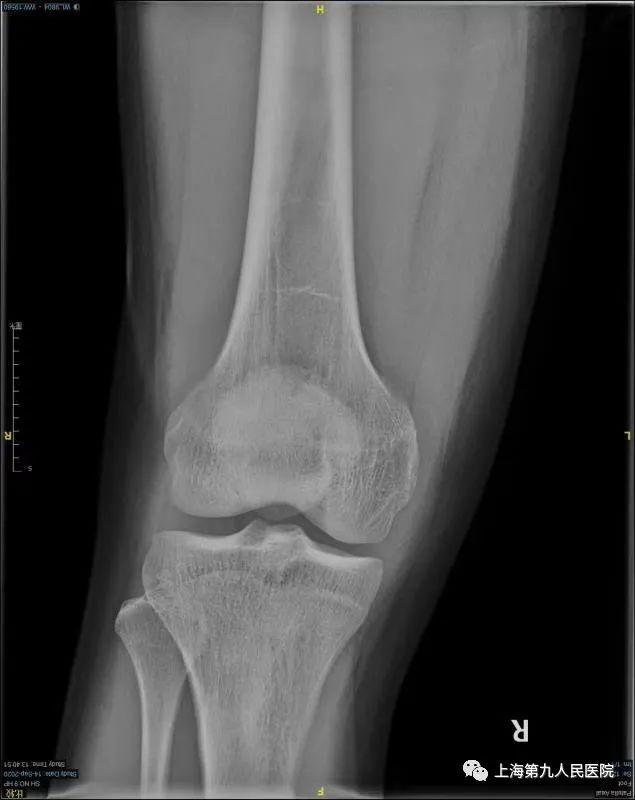

好多膝关节疼痛的朋友到医院寻诊时,医生多会让做一个膝关节的X线检查,就是下方这两张X线片,一张正位片、一张侧位片。

每个人的膝关节是由3块骨头加上一些软骨、韧带等软组织组成的。这3块骨头分别是股骨(大腿骨)、胫骨(小腿骨)和髌骨(膝盖骨)。每块骨头的表面有一层软骨,软骨富有弹性而又光滑,并且没有神经支配,有利于骨头之间无痛而又圆滑的摩擦活动;另外,在股骨和胫骨中间有两个垫片,叫作半月板,有调节冲击力的作用,并让骨表面之间更贴合。在日常生活中,健康的软骨和半月板保证我们的膝关节能够顺畅的完成各种活动。二

全身任何关节都可能发生骨关节炎,由于膝关节使用频繁、活动多、承受体重大等因素,发生骨关节炎更为常见。发生膝骨关节炎的朋友通常表现为关节疼痛、僵硬、肿胀,活动后疼痛加重,休息后有缓解,遇见寒冷、潮湿环境疼痛会加重。有些人平时走路还可以,但是上下台阶、起坐马桶或椅櫈困难;有些人平时疼痛症状轻微,而在一个轻微的扭伤后就出现关节显著的疼痛肿胀,长时间不能缓解。比如,66岁的王阿姨,平时身体没啥毛病,就是左侧膝盖痛了5年多,时好时坏,一开始出现关节疼痛后休息几天就好了,平时也没当回事。后来上下楼梯疼痛明显,平地上也走不远了,还变成了罗圈腿,最近半年关节疼痛更明显,有时晚上睡觉也疼,这样就很少出家门,生活影响很大。1月前到医院检查,拍X线片看到膝关节已经明显退变,缝隙变窄,磨损严重,骨质增生。